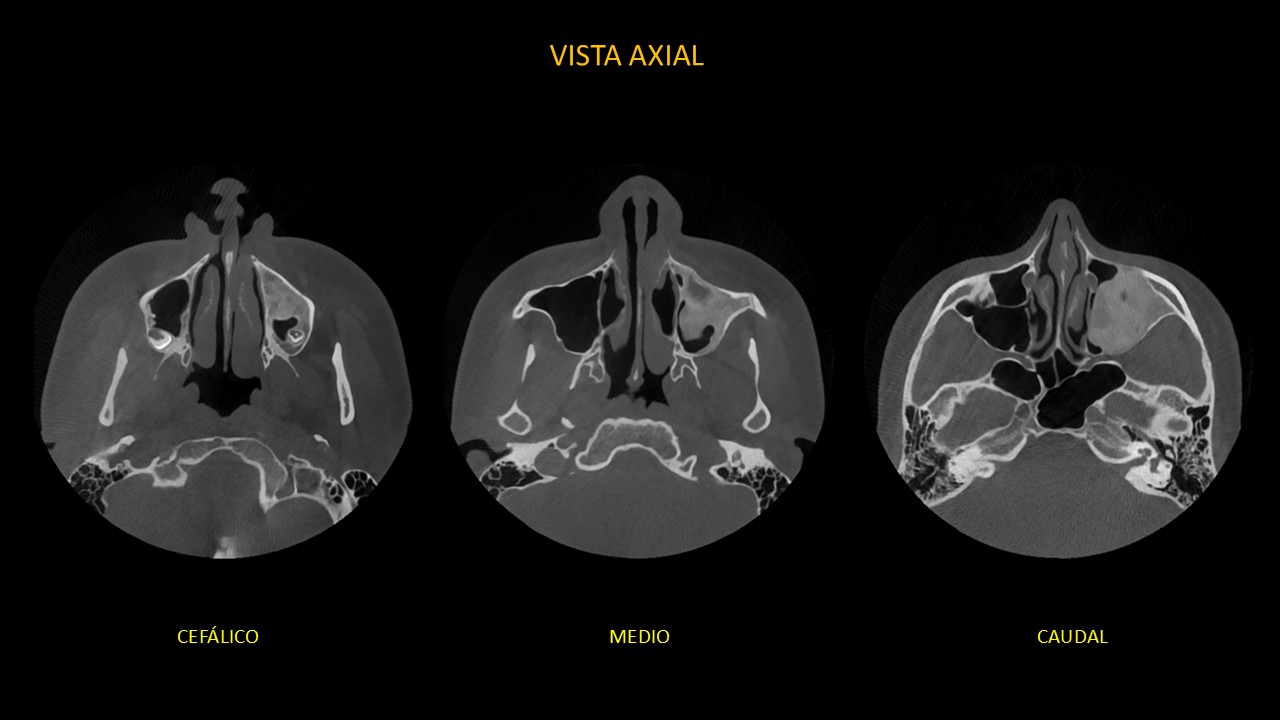

Figura 2

En cortes axiales (Figura 2), en un barrido de cefálico a caudal se observa desplazamiento medial de la pared lateral de fosa nasal izquierda, adelgazamiento y borramiento parcial de la cortical de la pared anterior, lateral, posterior y cortical basal del seno maxilar.